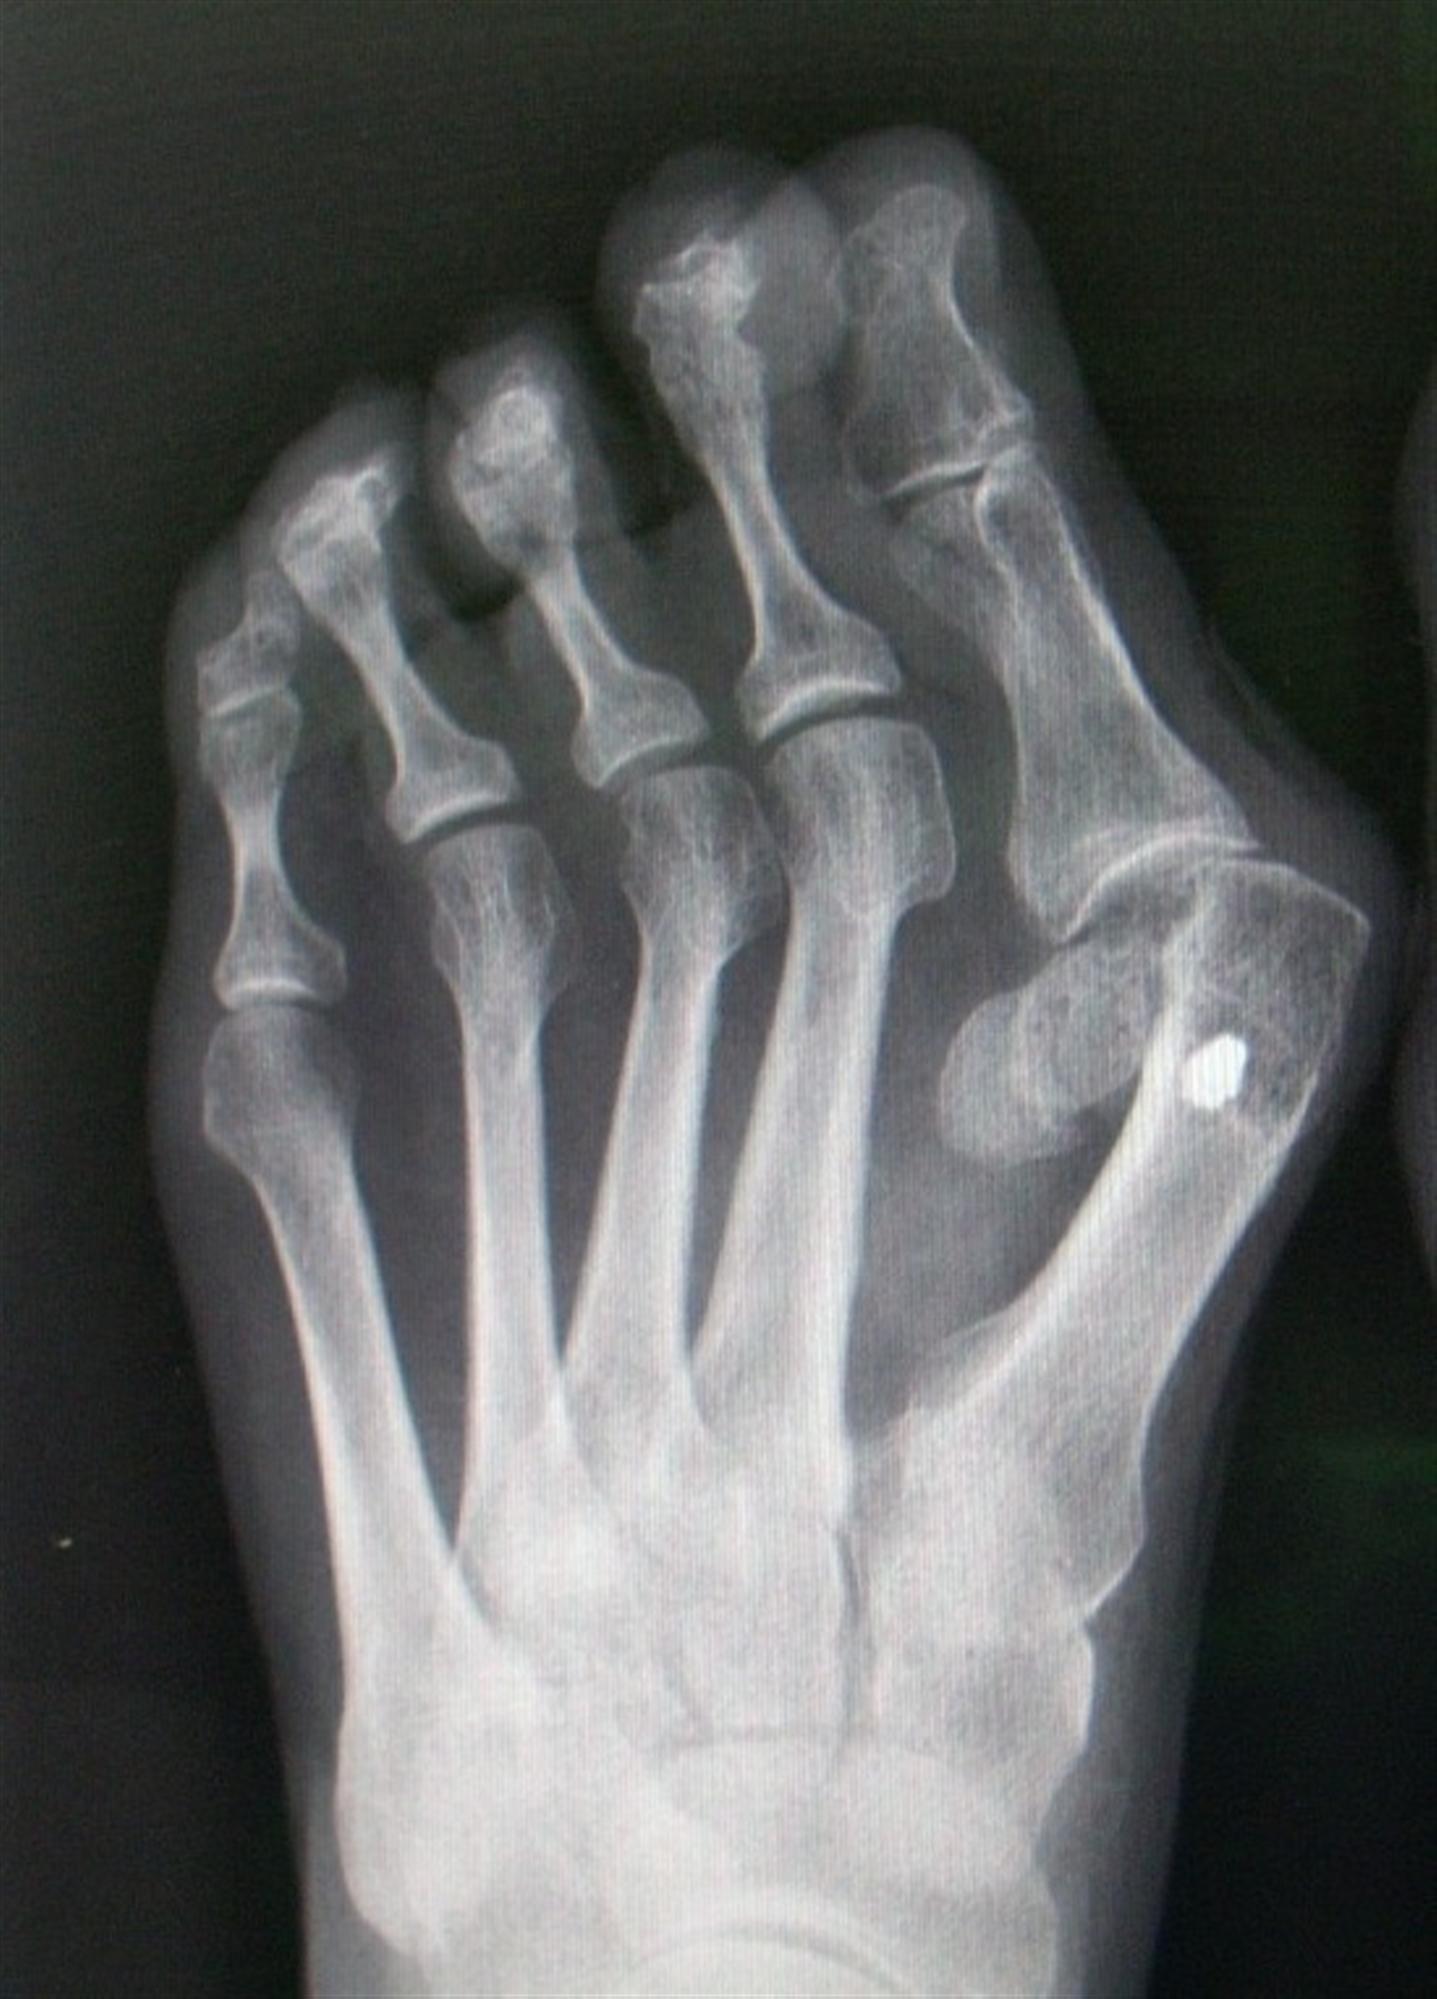

Foot Trauma, fracture of the interphalangeal joint of the great toe Foot Hallux Definition A bunion is a bony bump that forms at the base of your big toe. It is usually due to. It is made up of two phalanges , a proximal and a distal one. [2] the big toe often bends towards the other toes. The mtp joint is where the base. Hallux valgus (hv) is considered to involve the following:. Foot Hallux Definition.

sesamoid bone The Foot and Ankle Online Journal Foot Hallux Definition Hallux valgus (hv) is considered to involve the following: Halluces valgi) is a fixed abduction of the first metatarsophalangeal joint of the great toe. Hallux valgus, commonly referred to as a bunion, is a complex valgus deformity of the first ray that can cause medial big toe pain and. It is made up of two phalanges , a proximal and. Foot Hallux Definition.

Amputation through foot Semantic Scholar Foot Hallux Definition The great toe or hallux is located on the medial side and represents the first digit of the foot. A bunion is a bony bump that forms at the base of your big toe. The mtp joint is where the base. Hallux valgus, commonly referred to as a bunion, is a complex valgus deformity of the first ray that can. Foot Hallux Definition.